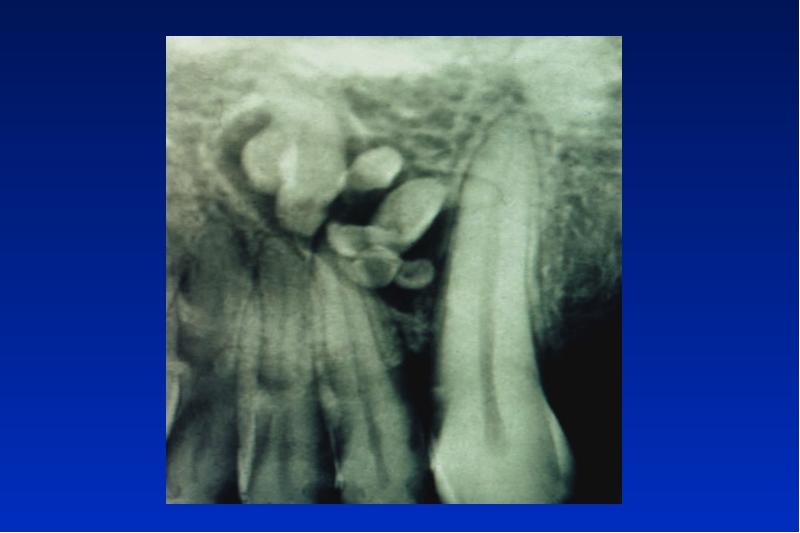

- 56. Odontom complex = gemischt compound

- 59. Kalzifizierende odontogene Zyste Odontogener Ghost cell Tumor zystisch oder solid gebaut